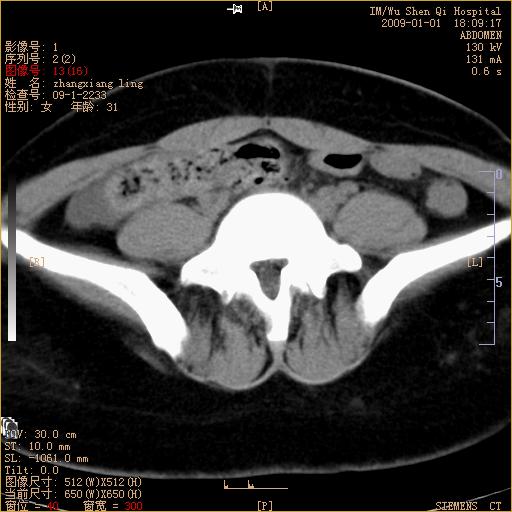

标题: CT17527:F31Y,腹痛伴血便9小时 [打印本页]

标题: CT17527:F31Y,腹痛伴血便9小时

升结肠肠壁不规则增厚,肠腔狭窄,考虑升结肠占位,建议增强扫描

升结肠肠壁不规则增厚,肠腔狭窄,考虑升结肠占位,建议增强扫描,不除外肠套叠.

升结肠肠壁不规则增厚,似呈同心圆改变,其有积液。结合病史首先考虑肠套叠伴肠壁坏死可能性大,结肠肿瘤待排。

患者已手术,结果肠系膜血栓形成肠坏死

结果:患者已手术,结果肠系膜血栓形成肠坏死。回过头再看局部肠壁增厚有分层(高密度坏死及低密度水肿)表现。